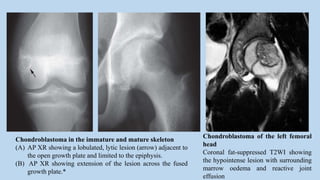

Chondroblastoma of the left femoral

head

Coronal fat-suppressed T2WI showing

the hypointense lesion with surrounding

marrow oedema and reactive joint

effusion

Chondroblastoma in the immature and mature skeleton

(A) AP XR showing a lobulated, lytic lesion (arrow) adjacent to

the open growth plate and limited to the epiphysis.

(B) AP XR showing extension of the lesion across the fused

growth plate.*